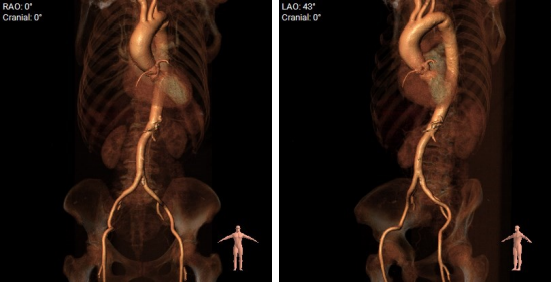

CT评估

1.瓣环及左室流出道。

2.主动脉瓣根部(左右瓣叶长度均超过冠脉高度)。

3.主动脉弓分析及瓣叶长度(最短弓距小于70mm)。

4.外周血管入路